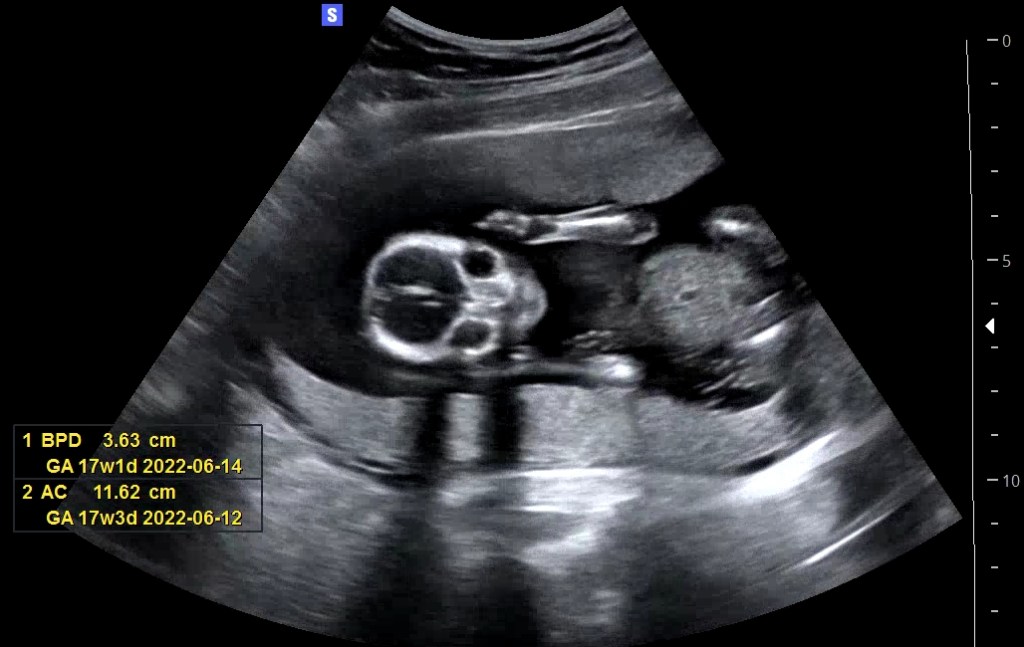

Our baby at 16+2!